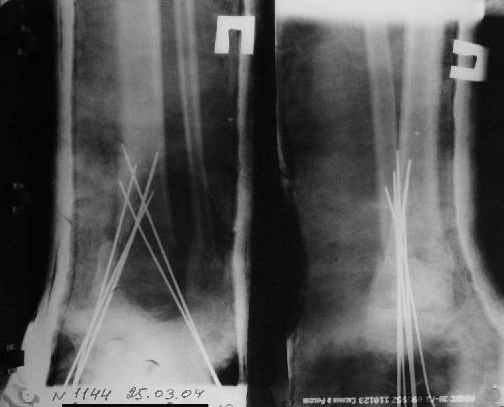

Перелом костей н\3 правой голени со смещением. Перелом большеберцовой кости можно охарактеризовать как компрессионно-оскольчатый.

Скелетное вытяжение за пяточную кость.

Так как речь зашла непосредственно о травме, см этапные

снимки. Как все было

Первичные